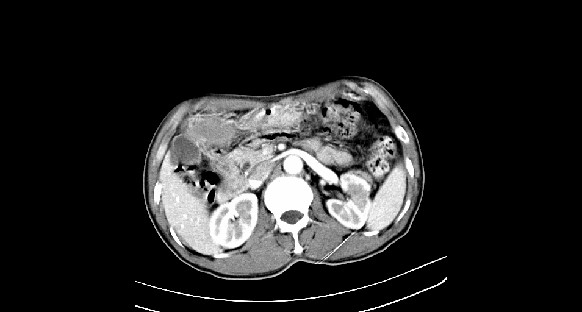

男性,70岁,体检b超发现左肾占位,请各位战友发表一下观点

左肾有两个病灶,且较大的病灶内可见点状钙化灶,增强扫描边缘也是呈渐进性强化,中央部分未见明显强化

a期明显强化,右肾小癌肿可能

右肾癌,建议病检!